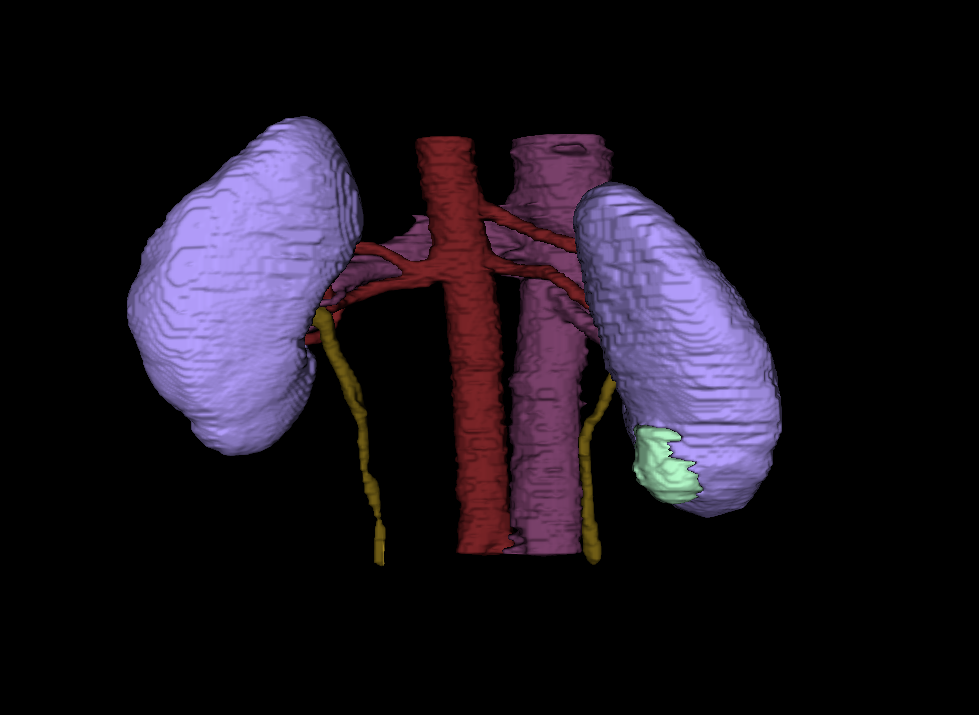

Heller is a PhD student conducting computer science research at University of Minnesota. His research focuses on using computer technology to enhance medical imaging, like a CT scan or an MRI. According to Heller, the magnified images will allow radiologists to quantify the type of tumor it is, saving time between a patient’s diagnoses and treatment.

“They will be able to measure a tumor mass, determine how big and rough they are, and whether they look distinct or blurry against the background. Medical professionals can use that information to choose the most effective treatment and predict a patient's outcome,” Heller explains.

(Courtesy: Nick Heller)

“Then we can turn those numbers into a computer code. If we can automate the code with images and equipment, a radiologist can just hit a button and receive information on the tumor, rather than looking at the image and making a judgement call,” Heller states.